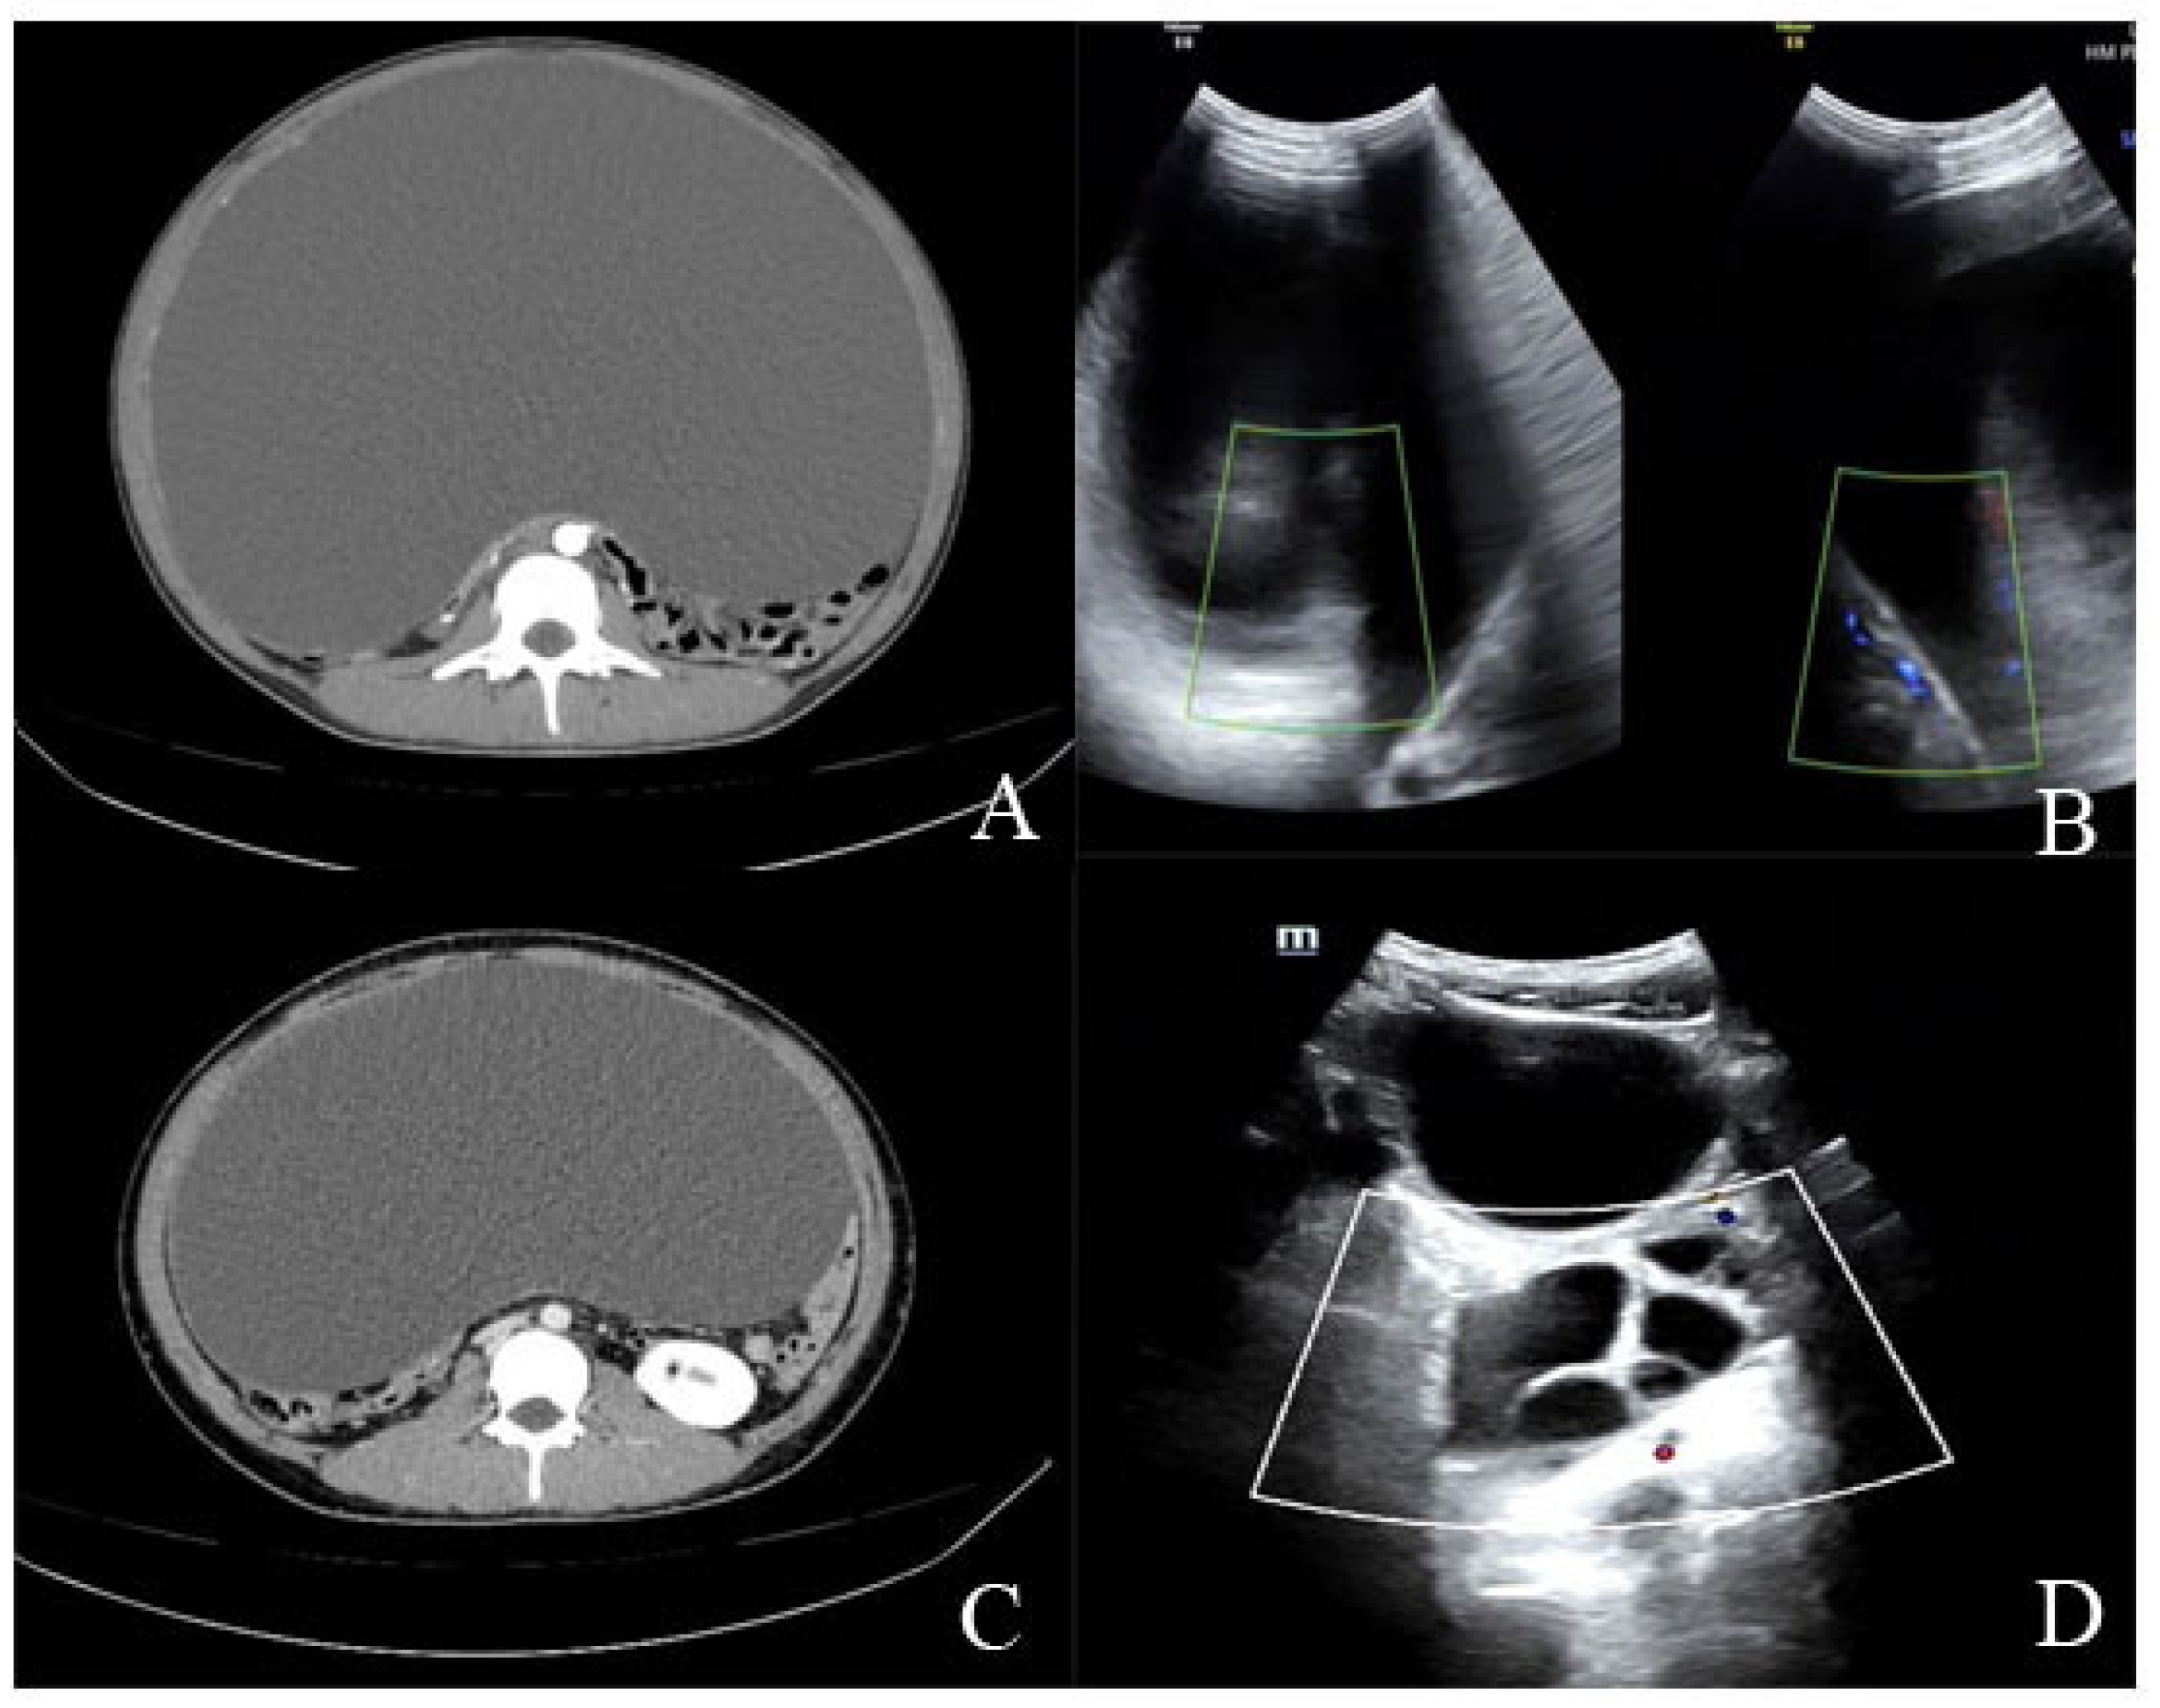

2.1.2. Diagnostic Workup

2.2.2. Diagnostic Workup

| Imaging findings | Large ovarian cystic mass with a maximum diameter of about 35 cm | Large ovarian cystic mass with a maximum diameter of 43 cm |